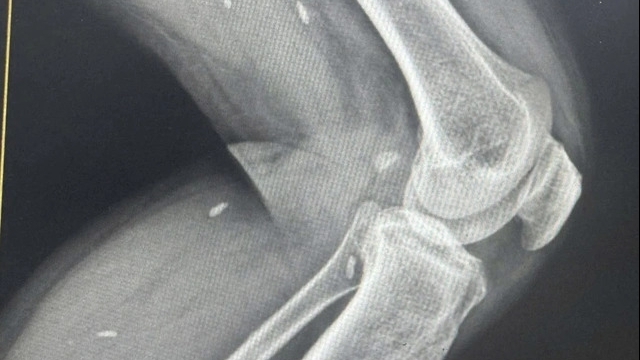

Hai bệnh nhân vào viện trong tình trạng bị ảnh hưởng bởi nguồn điện dẫn truyền từ tia sét, không trực tiếp đánh vào người, cho nên vẫn tỉnh táo, có triệu chứng tê, đau ở dọc cánh tay bên tiếp xúc nguồn điện do tia sét phóng ra.

Ngay khi tiếp nhận bệnh nhân, các y, bác sĩ Bệnh viện Đa khoa Thanh Oai đã khẩn trương thực hiện các biện pháp cấp cứu kịp thời như thăm khám tình trạng bệnh nhân, đặt đường truyền, thở ô-xy, theo dõi các dấu hiệu sinh tồn, rối loạn nhịp tim qua máy monitor, giải thích và trấn an tinh thần bệnh nhân, điện tim cho bệnh nhân...

Hiện tại, cả hai bệnh nhân đã qua cơn nguy kịch, các chỉ số sinh tồn ổn định hơn và đang được tiếp tục theo dõi, điều trị tại Khoa Hồi sức cấp cứu.